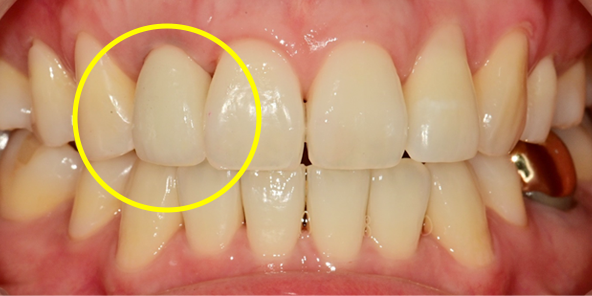

일상생활이 가능하도록 임시 보철물 완성

회복이 빠른 최소 절개 식립